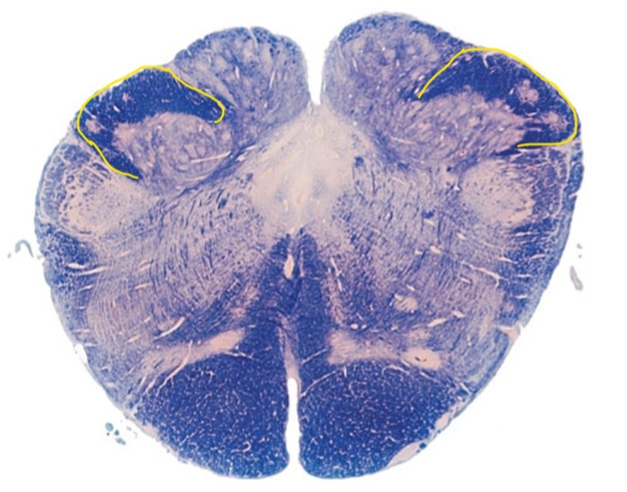

4

This section is through the _________________?

A

rostral pons

5

The outlined structure is?

corticospinal tract

6

The highlighted structure is?

superior colliculus